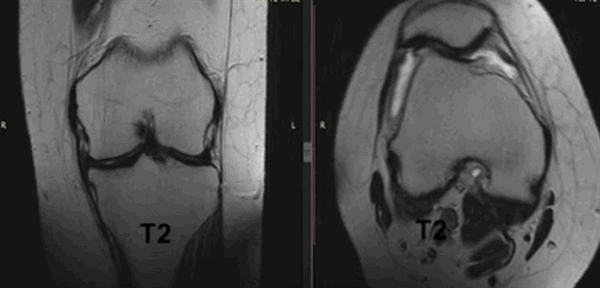

Варианты просмотра коленного сустава при МР-сканировании в разных проекциях (Т2 ВИ)

МРТ коленного сустава в прямой проекции. Определяется избыточное наличие синовиальной жидкости (яркий сигнал) на фоне разрушения мениска и нарушения конгруэнтности костей и их деформации.